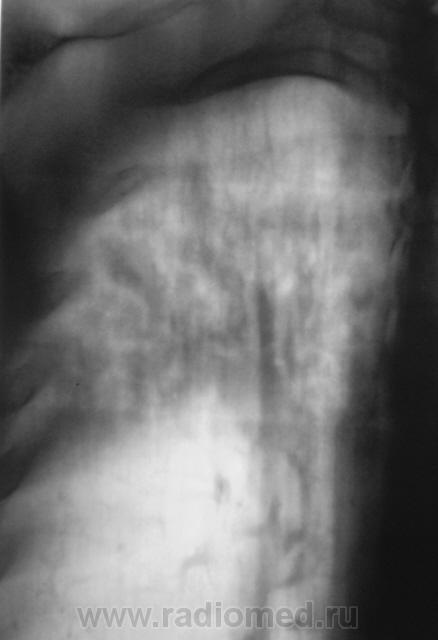

Томограммы.

Так может быть, без предварительного противовоспалительного лечения - сразу к фтизиатрам?

Да учитывая объём, клинику (отсутствие таковой), можно и сразу к фтизиатрам, но они, мне кажется, полечат сначала антибиотиками.